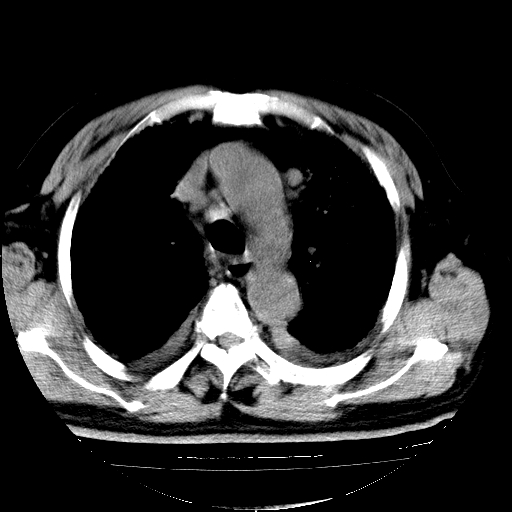

男,68岁,咳嗽、胸闷、发烧三天,查体:双肺散在湿罗音。

慢支合并感染.间质纤维化,双侧少量胸腔积液.

慢支合并感染.间质纤维化,双侧少量胸腔积液

慢支合并感染.间质纤维化,心衰双侧少量胸腔积液

支持 慢支合并感染.间质纤维化,心衰双侧少量胸腔积液.